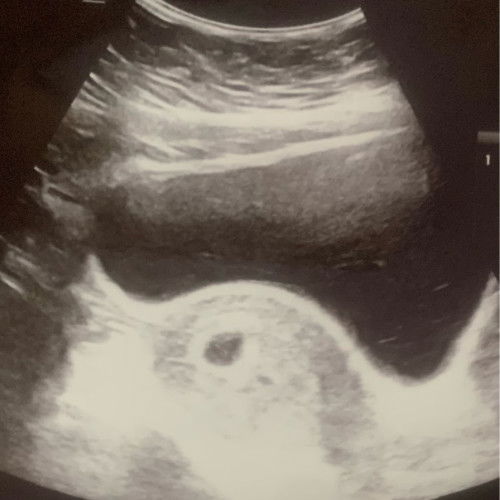

Hi mommies, 2 hari lepas saya disahkan keguguran bile kluar lendir pink kecik ja waktu pagi. Blah ptg saya pegi scan di klinik kali kedua terus xnmpk janin dah, refer ke emergency hospital pun dorg scan perut xnmpk janin scan tvs pun xnampak janin.. dok conclude maybe chemical pregnancy or janin dah keluar saya yg tk prasan but sepnjang kehamilan xpenah plak keluar darah ke spotting brown atau pink dan 100% takde rasa sakit ape2.. doc pun pening..nk ckp hamil kantung kosong pun tidak sbb first time scan semuanya elok n nmpk janin plus jantung dia.. so saya pun dgn sedih hati balik la sbb doc bg 2 minggu utk kantung kosong tu turun.. esoknya baru la start turun darah ketul2 sikit mcm period tpi masih tk sakit pape..keesokkan nya pkul 3 pagi perut sakit sgt mcm sengugut tahap ape ntah.. sejam kemudian lg kerap sakit tu dtg, 5 mnit sekali.. rasa dah tk waras dah time tu sakit sangat tiba2 rasa something mcm nk kluar saya tadah je ngn besen xsmpt nk dduk pun maka terkeluarlah darah termasuk janin (janin sempurna) sedih plus gembira saya tgk.. saya dah cuci dan niat utk tanam sbb sifat dia sempurna.. amek gmbr jgk utk bukti dkt hospital yg janin dah kluar..ternyata bukan chemical pregnancy tpi xtau la kenapa scan xnmpk apa.. wallahualam.. dah kluar tu mmg lega tuhan saja yg tau.. skrg saya dah mula proses berpantang.. perut sengal2 sikit la kalau nk bgun atau dduk selain dari tu semua okay.. cume sakit kepala la 😌 kalau ade dlm ni yg ade pengalaman berpantang bersalin atau keguguran boleh share tak mcm mne nk kurangkan sakit kepala.. saya dah minum air halia, ikat rambut tinggi2.. ke perlu jgk pkai param dan pilis? #pleasehelp